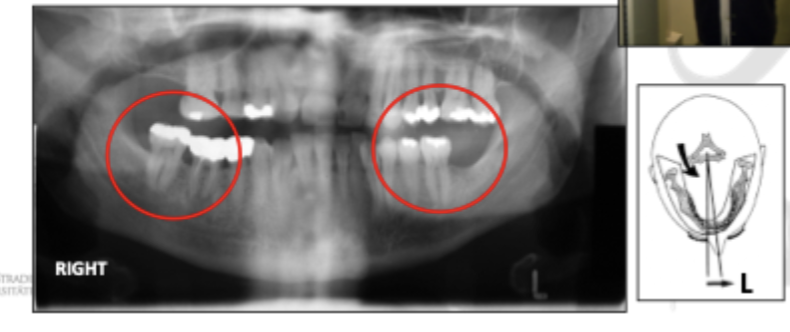

Patient position - Vertical error 1

Head & chin tipped down, frankfort plane not horizontal, occlusal plane distorted → Smiley

Patient position - Vertical error 2

Head & chini uppwards, frankfort not horizonral , occlusal plane distorted → Grumpy